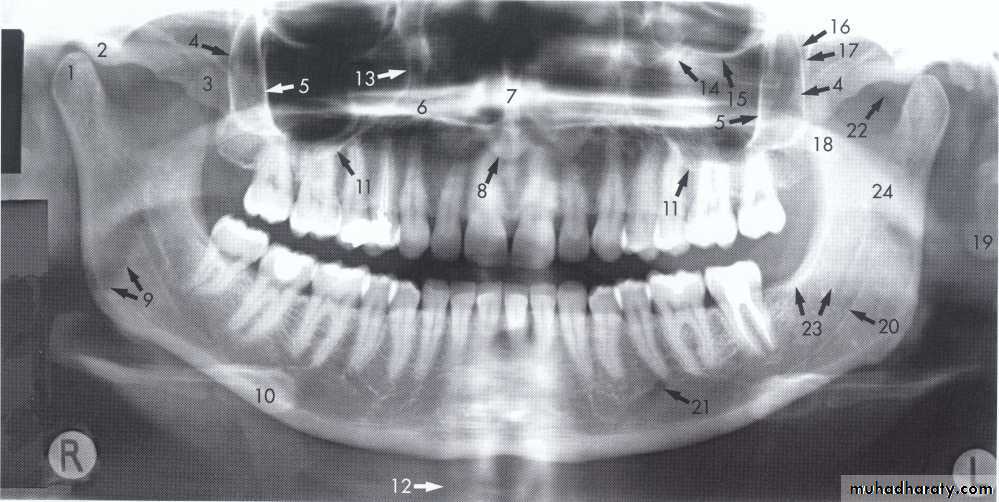

( hyoid bone, the hard palate, epiglottis).A dental panoramic tomograph showing the main real hard tissue shadows, including the plastic head support, drawn in on one side of the radiograph, NS — nasal septum,

MIT — middle and inferior turbinates, O — orbital margin, HP — hard palate, A — floor of antrum, Z — zygomatic arch, EAM — external auditory meatus, MP — mastoid process,

SP — styloid process, H — hyoid, P — plastic head support.

A dental panoramic tomograph showing the main real soft tissue and air shadows drawn in on

one side of the radiograph, NC — nasal cartilages, EL — ear lobe, SP — soft palate,DT — dorsum of tongue, Or — oropharnyx, NF — naso-labial fold, M — mouth.

A dental panoramic tomograph showing the main anatomical ghost or artefactual shadows drawn in on one side of the radiograph, PI — palate, Md — mandible, CV — cervical vertebrae.

1, Mandibular condyle. 2, Articular eminence. 3, Coronoid process of mandible superimposed on zygomatic arch. 4, Posterior wall of maxillary sinus. 5, Posterior wall of zygomatic process of maxilla. 6, Hard palate. 7, Nasal septum. 8, Tip of nose. 9, Dorsum of tongue. 10, Hyoid superimposed over inferior border of mandible. 11, Inferior border of maxillary sinus. 12, Image of cervical spine. 13, Medial border of maxillary sinus. 14, Infraorbital canal. 15, Infraorbital rim. 16, Pterygomaxillary fissure. 17, Anterior border of the pterygoid plates. 18, Lateral pterygoid plate superimposed over soft palate and coronoid process of mandible. 19, Ear lobe. 20, Inferior border of mandibular canal. 21, Mental foramen. 22, Posterior wall of nasopharynx. 23, Inferior border of mandible superimposed from opposite side. 24, Soft palate over mandibular foramen of mandible.